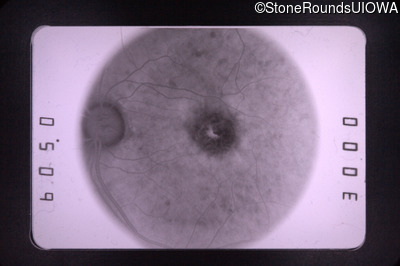

Fluorescein Angiography - Right - 20/70 -1 cc

Exemplar